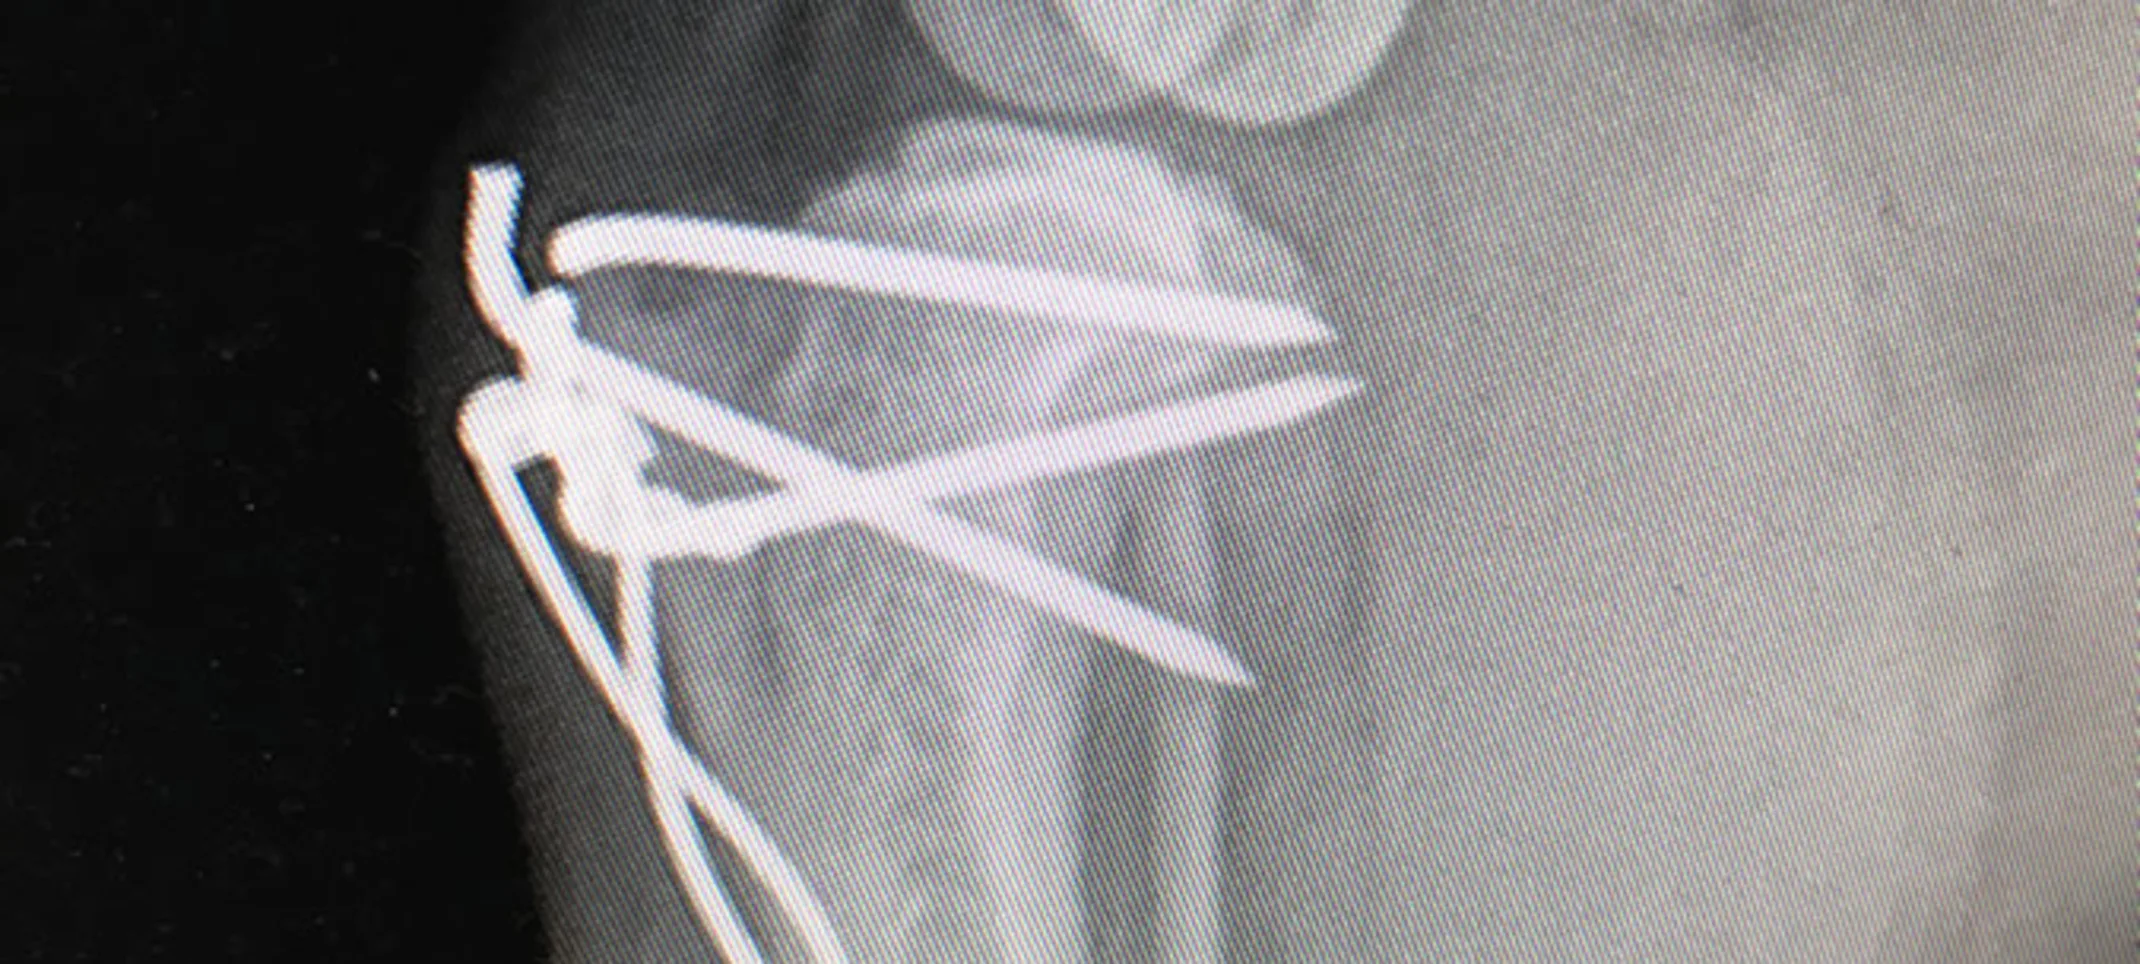

Patellar Luxation

Patellar luxation (dislocating kneecap) occurs when the knee cap dislocates and is both painful and a cause of chronic lameness and arthritis.

It can be traumatic and associated with cruciate ligament rupture or is seen as an inherited defect in certain small breeds of dogs like Yorkshire terriers. It is often bilateral (both legs affected) and is occasionally also seen in cats. Surgical correction of patellar luxation is a great way to reduce pain, improve leg alignment and reduce chances of arthritis.